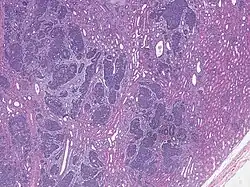

| High magnification micrograph showing the three elements of Wilms' tumor. H&E stain. | |

Pathologically, a triphasic nephroblastoma comprises three elements:[11]

- blastema

- mesenchyme (stroma)

- epithelium

Wilms' tumor is a malignant tumor containing metanephric blastema, stromal and epithelial derivatives. Characteristic is the presence of abortive tubules and glomeruli surrounded by a spindled cell stroma. The stroma may include striated muscle, cartilage, bone, fat tissue, and fibrous tissue. Dysfunction is caused when the tumor compresses the normal kidney parenchyma.

The mesenchymal component may include cells showing rhabdomyoid differentiation or malignancy (rhabdomyosarcomatous Wilms).